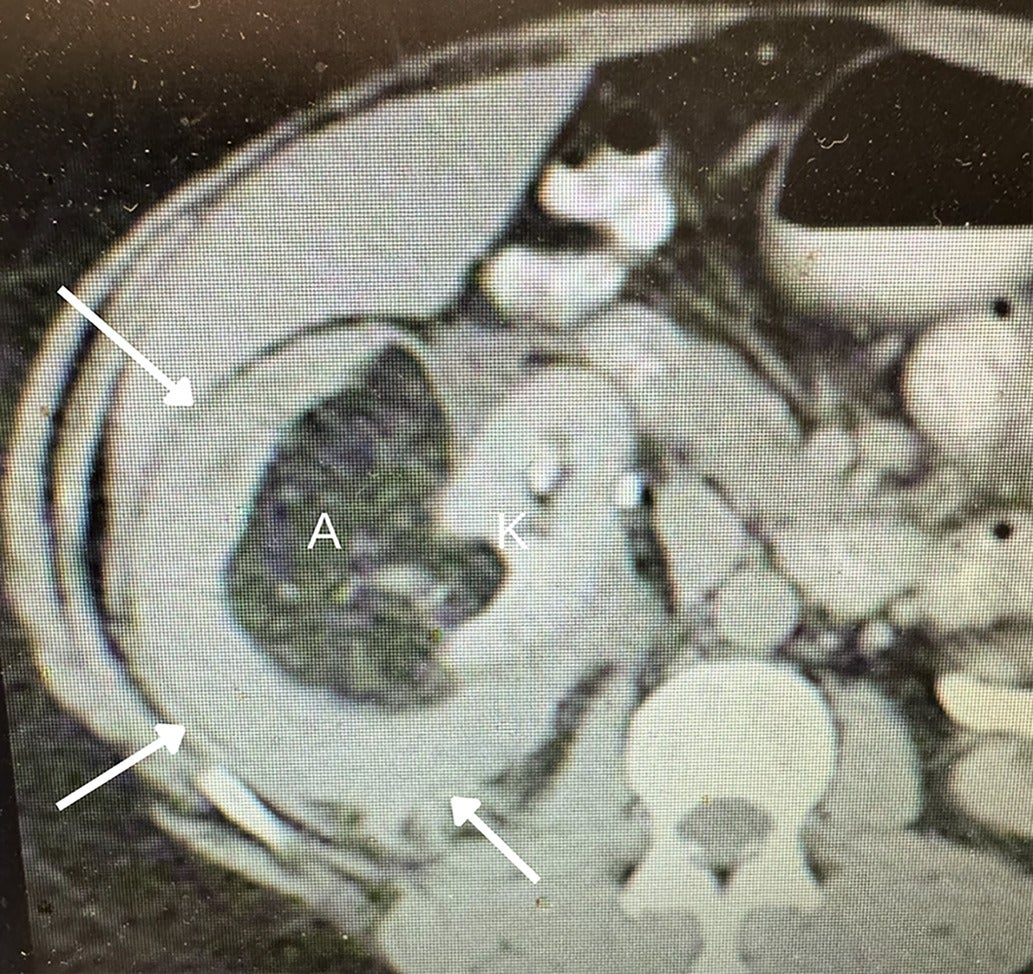

Fat-poor angiomyolipoma (fpAML) with angular interface. CT scan (A) showing the right kidney [K] with a simple cyst [C] and a fpAML [A]. The Hounsfield unit of the fpAML was 50 and identical to the HU of the adjacent muscle [M]. US showed this fpAML (B) to have mixed echogenicity, with an angular interface (arrows) and some overflow of the renal cortex (curved arrow, K = kidney). US of peripheral AMLs (C), which, like fpAMLs, often have the “overflowing beer” sign (arrows) with the renal cortex. The presence of either an angular interface or “overflowing beer” sign is helpful in distinguishing fpAMLs from renal cell carcinomas.

As we discussed more extensively in Part I, morphological features help distinguish classic AML from RCC on US, and they can similarly aid in differentiation of fpAML.1 Kim et al found that on contrast-enhanced CT of renal masses <4 cm, an angular interface had a sensitivity of 55% and specificity of 81.9% for fpAMLs, while the “overflowing beer” (also referred to as the “drooping”) sign carries a sensitivity of 61% and specificity of 97.10 Strother et al demonstrated that both signs were strongly associated with fpAML, with odds ratios of 12.6 and 11.2, respectively ( Figure 1 ).11 Thus, when an angular interface or overflowing beer sign is present, the lesion is more likely an AML than RCC.